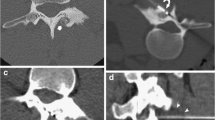

Cryoablation is another thermal ablation technology with particular biochemical and biophysical mechanisms of tissue destruction [13]. Room temperature argon gas is delivered through a sealed insulated probe. Rapid expansion of the gas results in cooling via the Joule-Thompson effect, with temperatures reaching just over −100°C at the exposed probe tip, and exceeding within a few seconds the effective temperature for cryoablation of a tumor (<−40°C). An ice ball is formed (Fig. 1) leading to the development of intercellular ice crystals. The change in electrolyte and osmotic pressure causes cell dehydration and damage to the cellular membrane with the development of intracellular ice crystals. Cytoclasis ensues with fragmentation, and the cell structure is completely destroyed [14]. During the cryoablation period, microvasculature membranes swell and break. When the temperature is recovered, a wide area of thrombus has formed in the local microcirculation. This leads to further lack of oxygen and necrosis of tissues [15]. Active thawing is achieved by the infusion of helium gas into the cryoprobes, instead of argon gas. Percutaneous cryoablation is widely used in the treatment of solid soft tissue tumors and more recently for musculoskeletal lesions including tumors involving bone [16, 17]. However, there are only limited data on image-guided percutaneous cryoablation in the treatment of osteoid osteoma [18, 19]. The rationale for why cryoablation of osteoid osteoma may be beneficial and potentially superior to radiofrequency ablation includes the following: patient tolerance without general anesthesia, intraprocedural ablation zone monitoring and control, preservation of critical structures/tissues, and improved pain management efficacy. The purpose of this study was to evaluate the safety and efficacy of CT-guided percutaneous cryoablation for osteoid osteoma in children.

Percutaneous cryotherapy was performed using a cryotherapy delivery system (Cryohit; Galil Medical, Yokneam, Israel), equipped with cryoprobes of 2.0 mm diameter (approximately equal to 14 gauge). A single cryoprobe was inserted coaxially through the access needle (Fig. 2). The access needle was then withdrawn slightly so that the distal 1 cm of the cryoprobe was exposed. A scan was obtained to confirm that the position of the cryoprobe tip was within 5 mm of the inner edge of the nidus (Fig. 3). To prevent skin injury, a small amount of filtered sterile gas (5–10 ml) was injected into the subcutaneous region of the puncture site and a heated sterile water bag was put on the skin near the puncture area. A warming mat was placed under the body of the patient to prevent a substantial decrease in body temperature. Two freeze-thaw cycles were performed for each lesion with a time frame of 8-min freeze, 5-min passive thaw intended for each cycle. During freezing, the cryoneedle tip temperatures reached −175°C (based on a thermocouple measurement).

The size of the ablation zone (ice ball) generated could be adjusted by the length of the noninsulated tip, amount of freezing time, and rate of gas delivered to the probe. The length of available noninsulated tips was 40 mm. Using the whole length of the cryoprobe tip (40 mm), a freezing time of 10 min, and 3,200 psi of argon, a 4 × 6 cm ice -ball is generated. If one-third of the tip was covered with the cannula of the biopsy needle, the volume of the ice ball would be decreased correspondingly by approximately one-third. As an example, for a 1 cm lesion, the ice-ball coverage should be about 2 cm, so the settings used would be as follows: cryoprobe tip length of 2 cm (that is the amount extending beyond the cannula), argon gas pressure of 3,200 psi, freezing time of 8 min, and thawing time of 5 min.

CT scanning was performed periodically to monitor for changes in surrounding tissues (Fig. 4). CT scanning was performed for lesion localization, needle targeting, and therapy monitoring. Cryoablation may be observed on CT imaging as a hypoattenuating area in the soft tissues and is less conspicuous within bone. Monitoring allows control of the cryoablation zone. There were no direct signs of inadequate coverage. Signs of complications were if the cryoablation zone was extending into adjacent critical structures such as neurovascular bundle, skin, or articular cartilage. Upon completion of the cryoablation, a 3-min active thawing was performed (instilling helium gas into the cryoprobes instead of argon gas), and the probes were removed. As an additional measure to prevent bleeding, a small amount of fibrin glue was inserted into the puncture hole. After the probe was removed, a final CT scan (2 mm thickness) was obtained to check for possible complications such as fracture or hematoma.

Results of the cryoablation are summarized in the Table 1. Percutaneous cryoablation was technically successful in all six patients. The mean time of cryoablation was 18 min (range 12–25 min) for each procedure. There were three cases where the cryoablation zone (ice ball) could be partially visualized within the soft tissues because of a superficial location of the osteoid osteoma and a portion of the active cryoprobe tip was situated within the adjacent soft tissues. The entire procedure duration ranged from 70 to 110 min (mean 90 min). The mean length of in-hospital stay for each admission was 3.5 days (range 3–5 days). All patients tolerated full weight-bearing and could function without limitation within 3 days after the procedure without need for casts or crutches. There were no fractures, hematomas, myoglobinuria, or neurovascular injuries during or immediately after the procedure. One minor complication was observed in a patient who demonstrated moderate fever, discomfort, and had body core temperature of 38°C for 1 day after the operation. These symptoms were relieved after 2 days of physical cooling and administration of acetylsalicylic acid. Significant pain relief was observed in all patients after the ablation. The VAS score averages were 6.57 ± 0.55 pre-procedure, 3.24 ± 0.23 on day 3 post-procedure, 1.54 ± 0.14 on day 7 post-procedure, and 0.57 ± 0.10 on day 30 post-procedure. The results of the t-test showed a statistically significant difference (P < 0.05) between the VAS of patients pre-procedure, and those at 3 days, 1 week, and 1 month post-procedure. The clinical success rate was also 100%, and for all six patients there was no evidence of recurrent symptoms at latest follow-up. No delayed complications (e.g., infection or myoglobinuria) were observed during the follow-up period. No skin changes were identified in the subjects who had superficial lesions treated. No major complications were encountered. For each patient, MRI after the procedure showed an area of signal alteration corresponding to the cryoablation zone (Fig. 5). These post-ablation MRIs depicted no complications that resulted from the procedure. No stress fractures were observed during the 18–36 month follow-up.